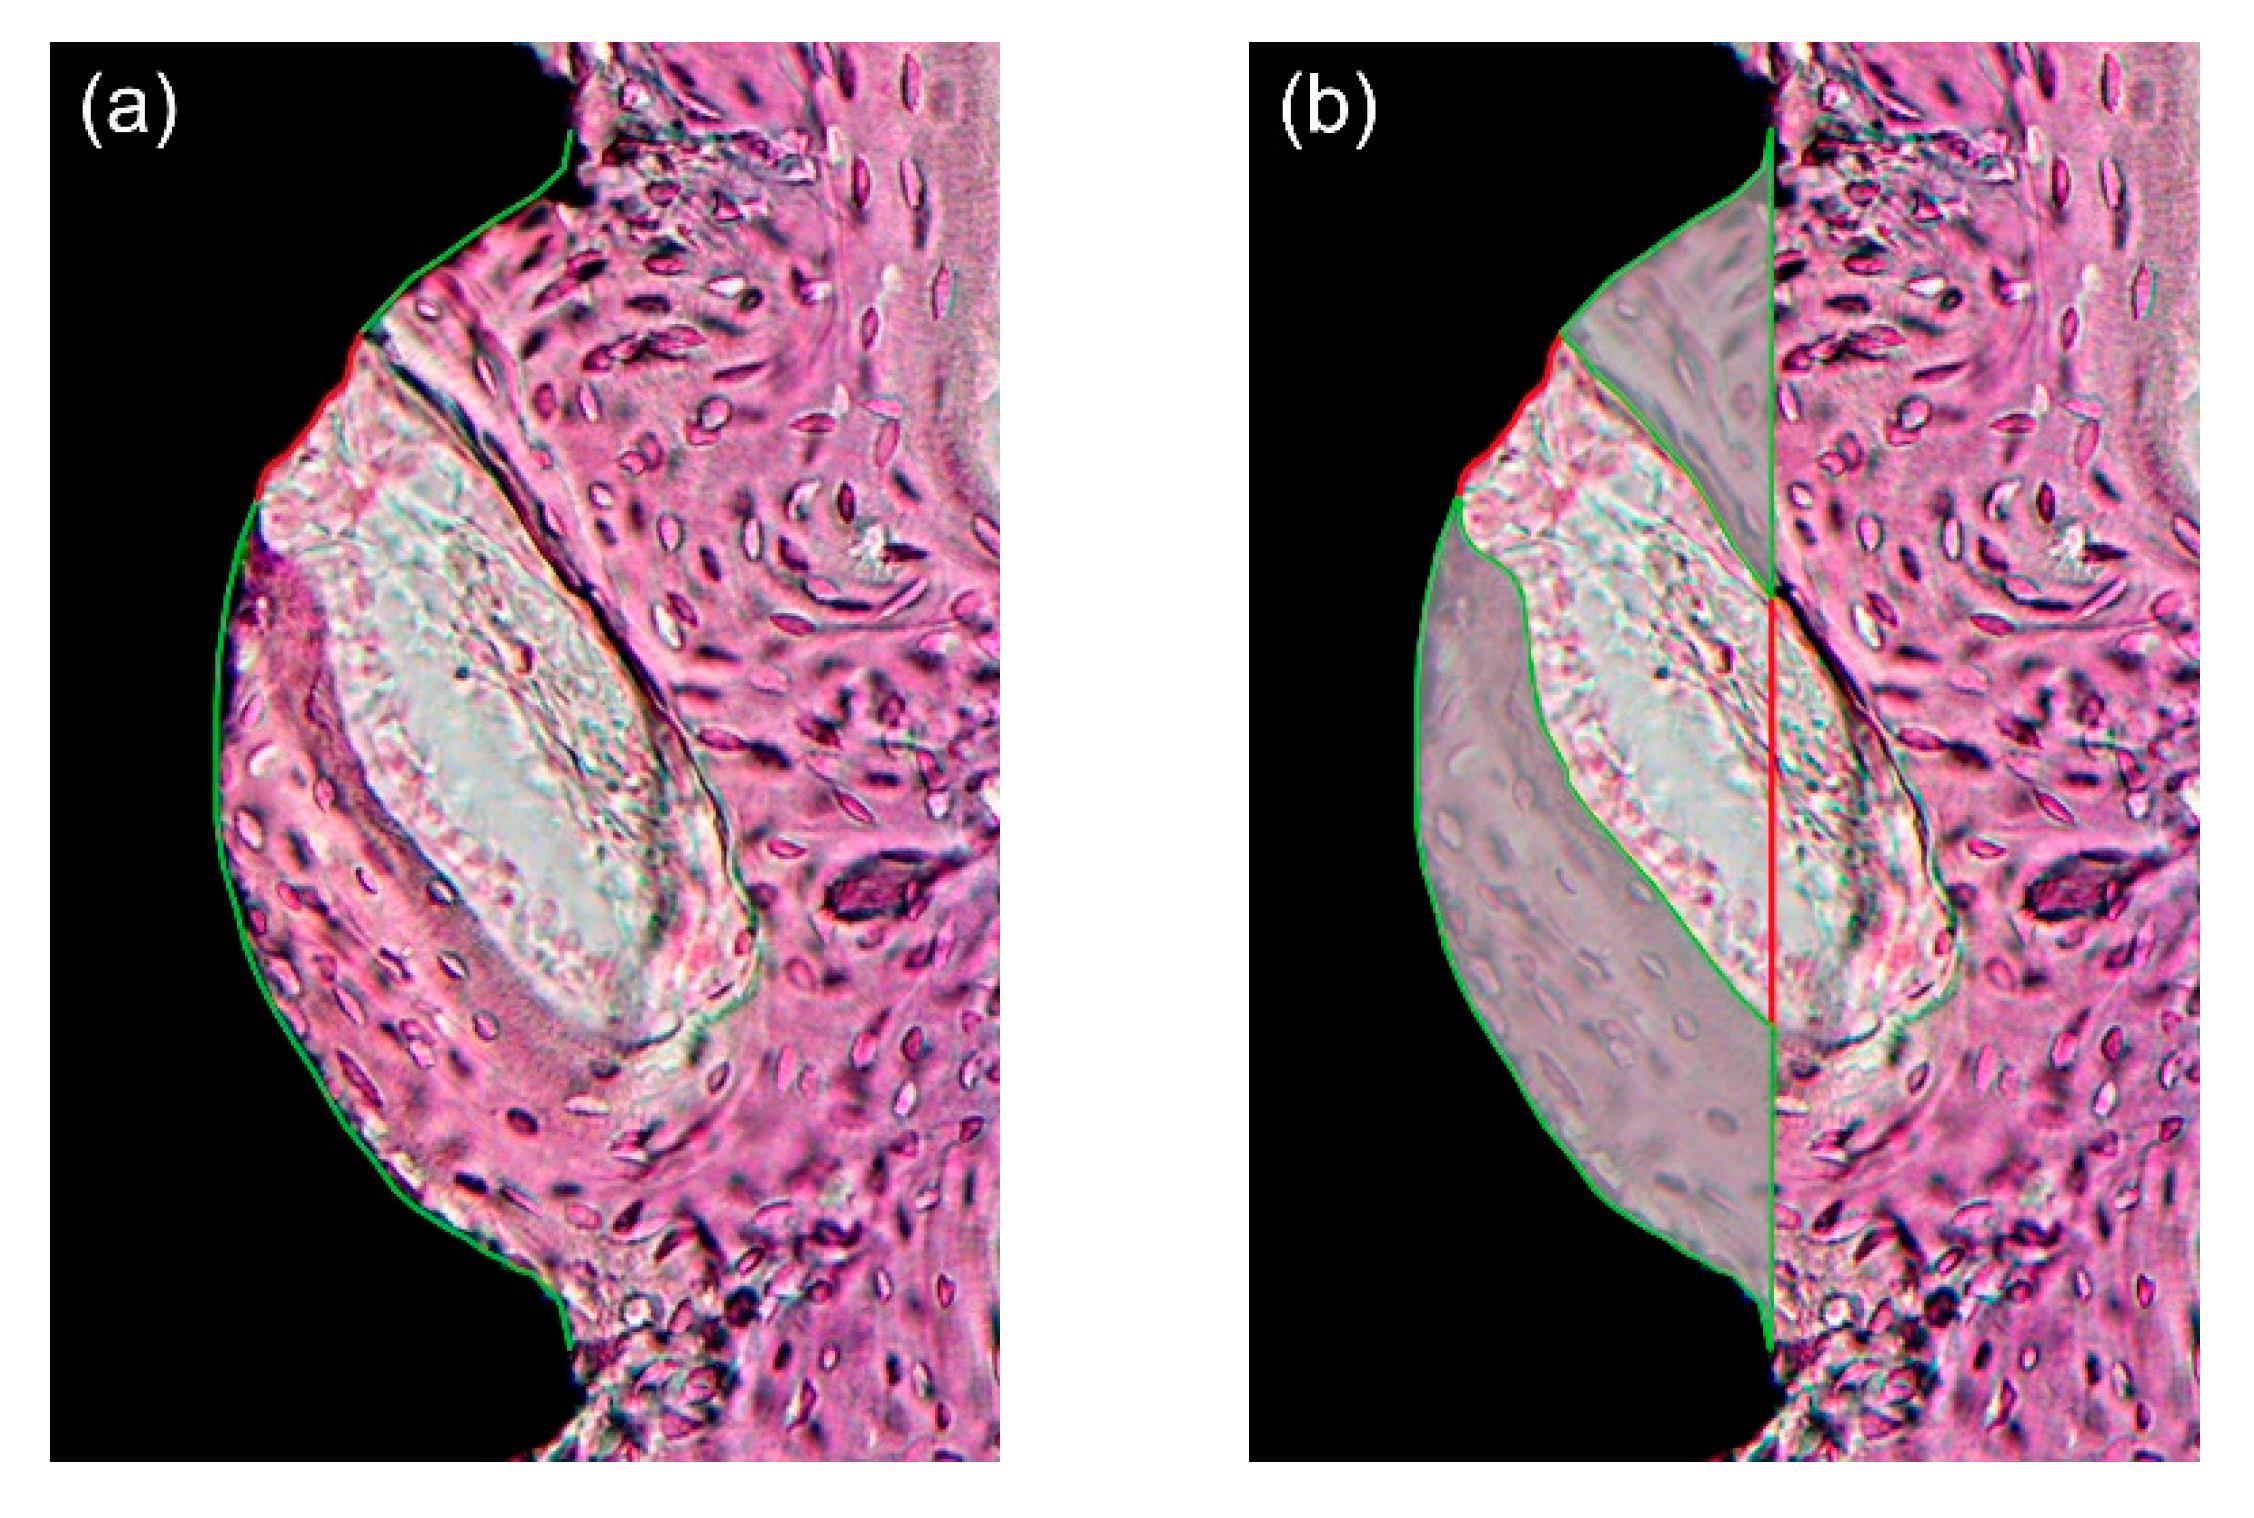

After microscopic observation, histological images were captured at 12.5× and 40× magnification using a digital camera (Polaroid DMC2 digital microscope camera, Polaroid Corporation, Cambridge, MA, USA) attached to a light microscope (Olympus BX50; Olympus Optical, Tokyo, Japan). Quantification was performed under 40× magnification with image analysis software (ImageJ; NIH, Bethesda, MD, USA; http://imagej.nih.gov/ij/index.html, accessed on 7 February 2021). As in previous studies, an area within the three best consecutive threads engaged in the upper cortical bone region was defined as the region-of-interest (ROI) [60,61,62]. The measurement followed the method suggested by Lee et al. [29] (Figure 4). Within the ROI, the following primary outcome measures were evaluated by two blinded and trained examiners (J.H.J. and K.C.O), and the average values were used for statistical analysis. BIC (%) was calculated as “bone contact length within threads/overall length of threads.” Bone area (BA, %) was calculated as “area of newly formed bone between threads/overall area between threads.”

Figure 4.

(a) Bone-to-implant contact (BIC, %) calculated by the length of the green lines divided by the total length of the well (green and red lines); (b) Bone area (BA) calculated by the area marked with green lines divided by the total area of the well. Note that the region-of-interest (ROI) was defined as an area within the three best consecutive threads engaged in the upper cortical bone, and therefore, a total of three threads were used for the calculation. Only one third of ROI is shown for simplicity.